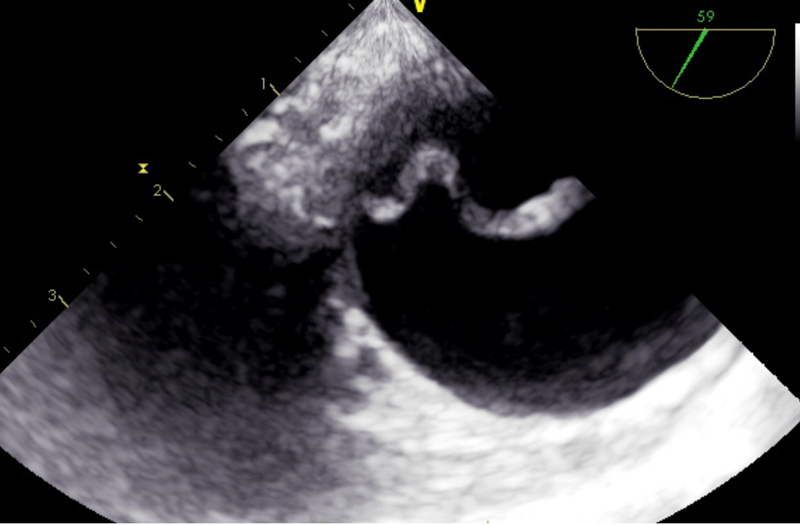

The portable TOE is advantageous in emergency situations with time constraints and in patients with haemodynamic instability, and overcomes the limitations of the TTE. However, the quality of TOE examination depends on the observer and their experience. False positive or false negative findings can arise easily when interpreted by unskilled individuals or a single person [47]. It also suffers from the poor spatial resolution and blind spots caused by intervening anatomical structures (fig. 2).

Figure 2 Transoesophageal echocardiographic image of the intimal flap in type A dissection.